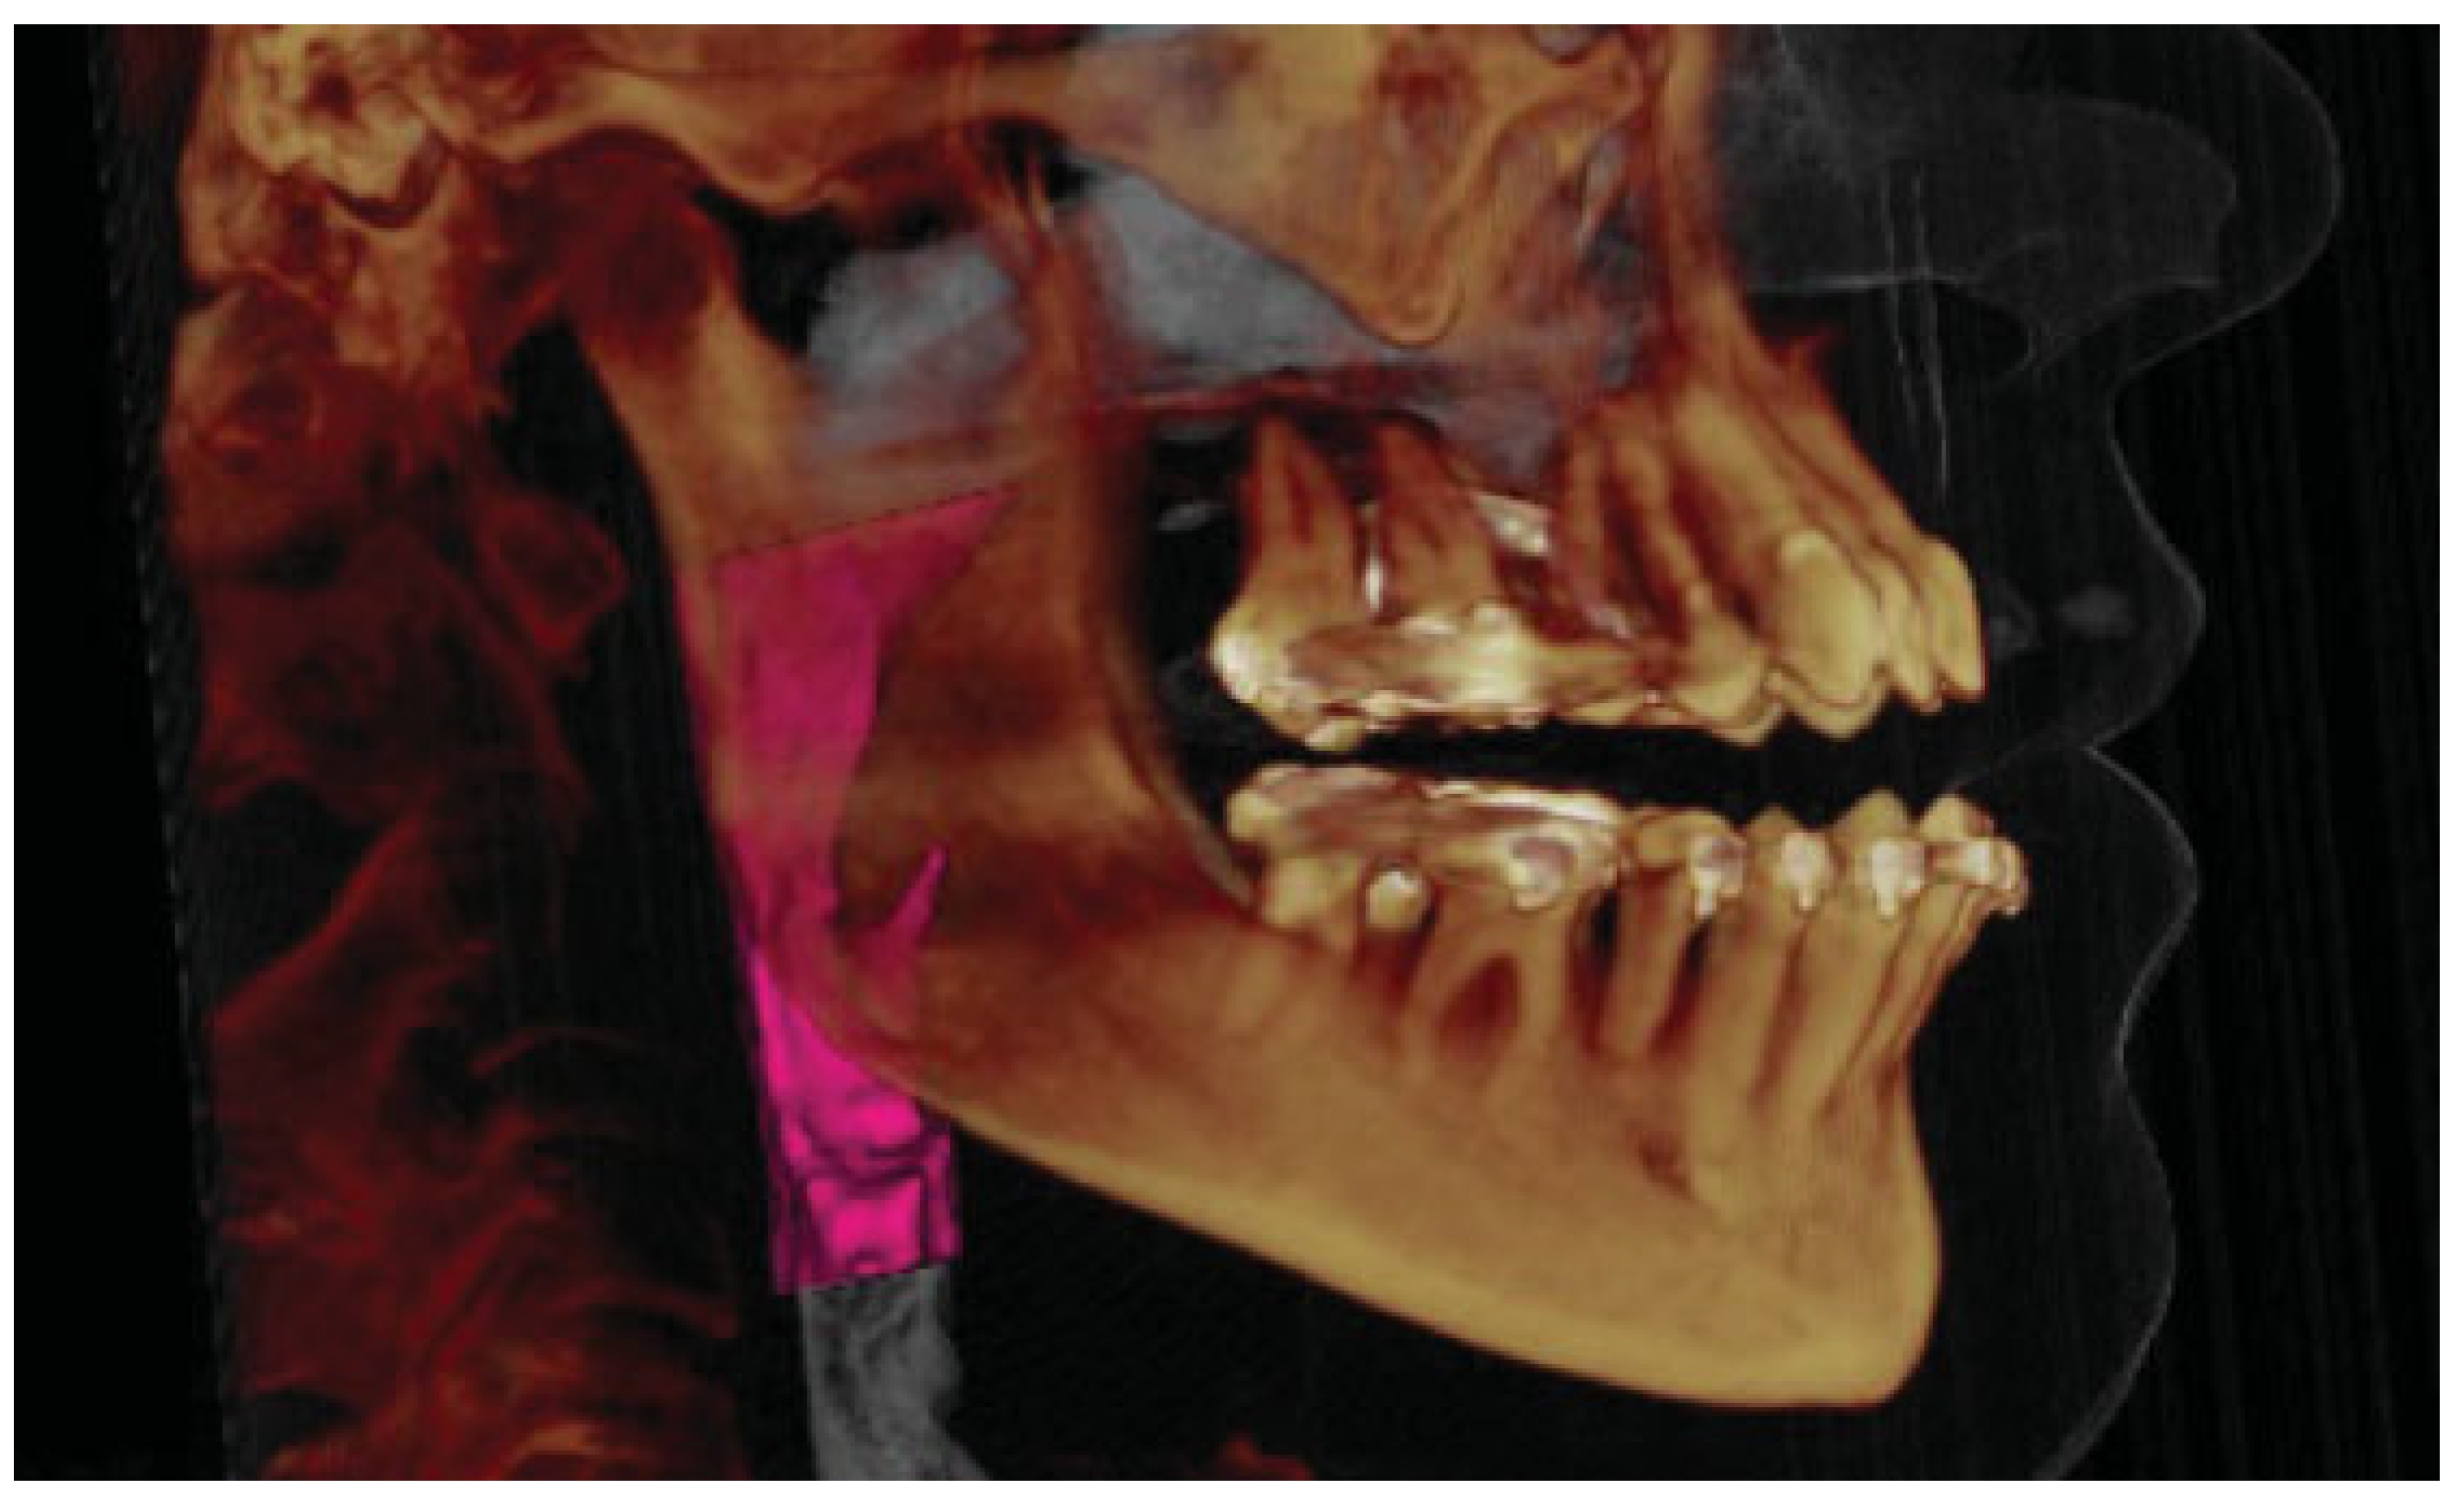

Comparison of Imaging Softwares for Upper Airway Evaluation: Preliminary Study

:Materials and Methods

Results